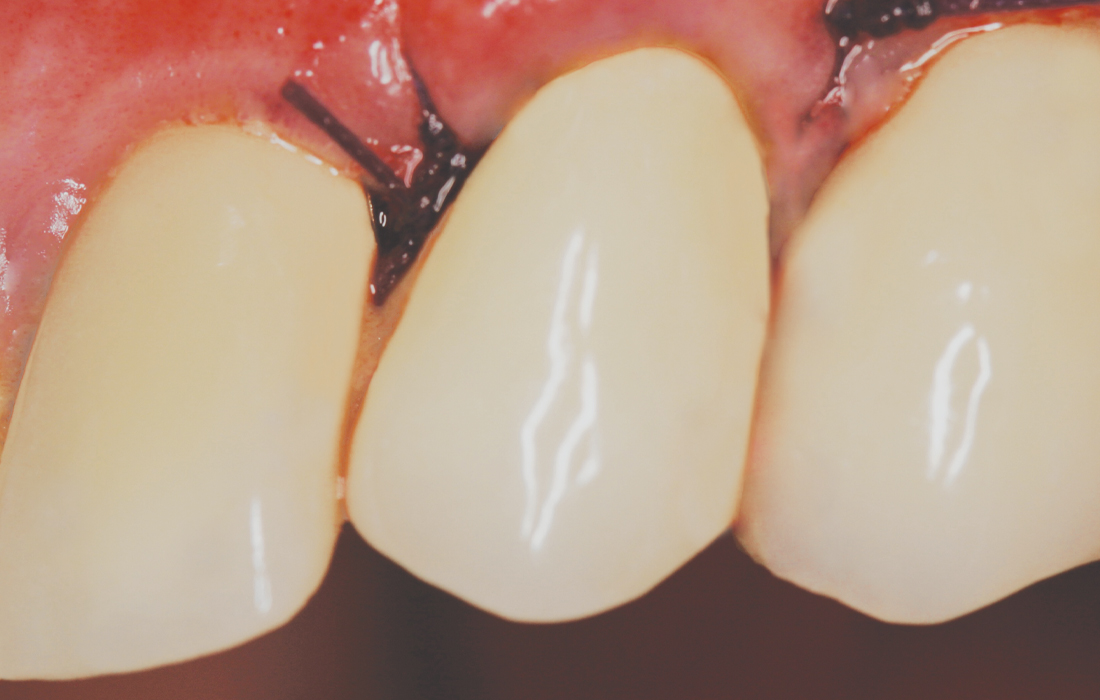

Bone Grafting Image 1 CSM V15I2

Bone Grafting Image 2 CSM V15I2-

Bone Grafting Image 3 CSM V15I2

Bone grafting can be essential to achieving a predictable outcome whether performing socket regeneration for future implantation or immediately placing an implant. Here, a fractured central incisor was removed, a Hahn Tapered Implant was placed, and the site was grafted with Newport Biologics™ Mineralized Cortico/Cancellous Allograft Blend material (Glidewell; Irvine, Calif.), which contributed to the esthetic final restoration.